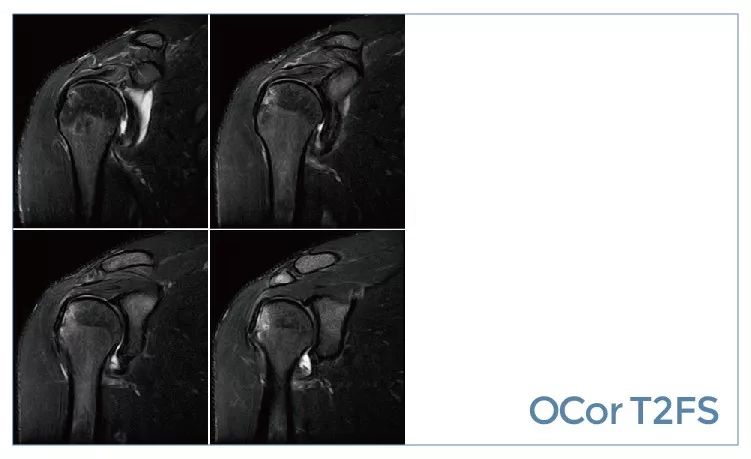

【朗润影像档案】20190927磁共振影像病例结果讨论